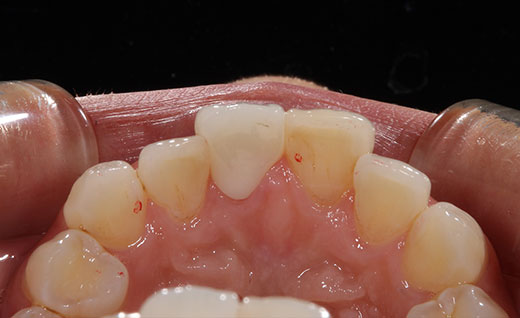

施術前

歯のホワイトニングを行われ白くなったのですが、以前に神経を抜いた前歯の色がすこし目立つようになってしまったので、今回オールセラミックで色を合わせさらにその横の歯の虫歯の治療も同時に行いました。